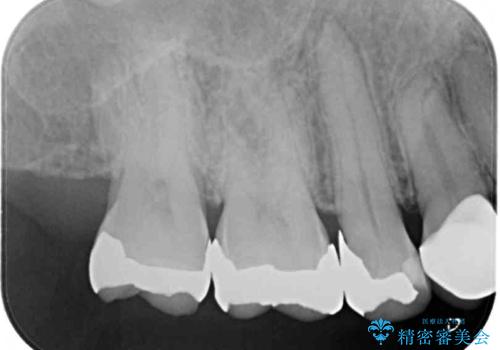

- 奥歯に痛みを感じるようになり、更にはその前の歯のセラミックが欠けてしまったとのことで来院された患者様です。

痛みがしばらく続いていたため、抜髄となる可能性を考慮しながら処置を行うこととしました。

銀歯の下の虫歯はそれほど大きくなく、初回の処置以降、痛みを感じることはなくなりました。

セラミックインレー装着後も痛みが生じることはなく、神経の状態も正常な反応が認められました。